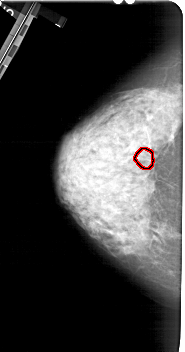

ics_version 1.0 filename A-1282-1 DATE_OF_STUDY 7 8 1995 PATIENT_AGE 54 FILM FILM_TYPE REGULAR DENSITY 4 DATE_DIGITIZED 7 7 1998 DIGITIZER HOWTEK 43.5 SEQUENCE LEFT_CC LINES 5266 PIXELS_PER_LINE 2761 BITS_PER_PIXEL 12 RESOLUTION 43.5 OVERLAY LEFT_MLO LINES 5491 PIXELS_PER_LINE 2971 BITS_PER_PIXEL 12 RESOLUTION 43.5 OVERLAY RIGHT_CC LINES 4951 PIXELS_PER_LINE 2461 BITS_PER_PIXEL 12 RESOLUTION 43.5 NON_OVERLAY RIGHT_MLO LINES 5446 PIXELS_PER_LINE 2776 BITS_PER_PIXEL 12 RESOLUTION 43.5 NON_OVERLAY |

FILE: A_1282_1.LEFT_CC.OVERLAY TOTAL_ABNORMALITIES 1 ABNORMALITY 1 LESION_TYPE MASS SHAPE ARCHITECTURAL_DISTORTION MARGINS SPICULATED ASSESSMENT 4 SUBTLETY 1 PATHOLOGY BENIGN TOTAL_OUTLINES 1 BOUNDARY |